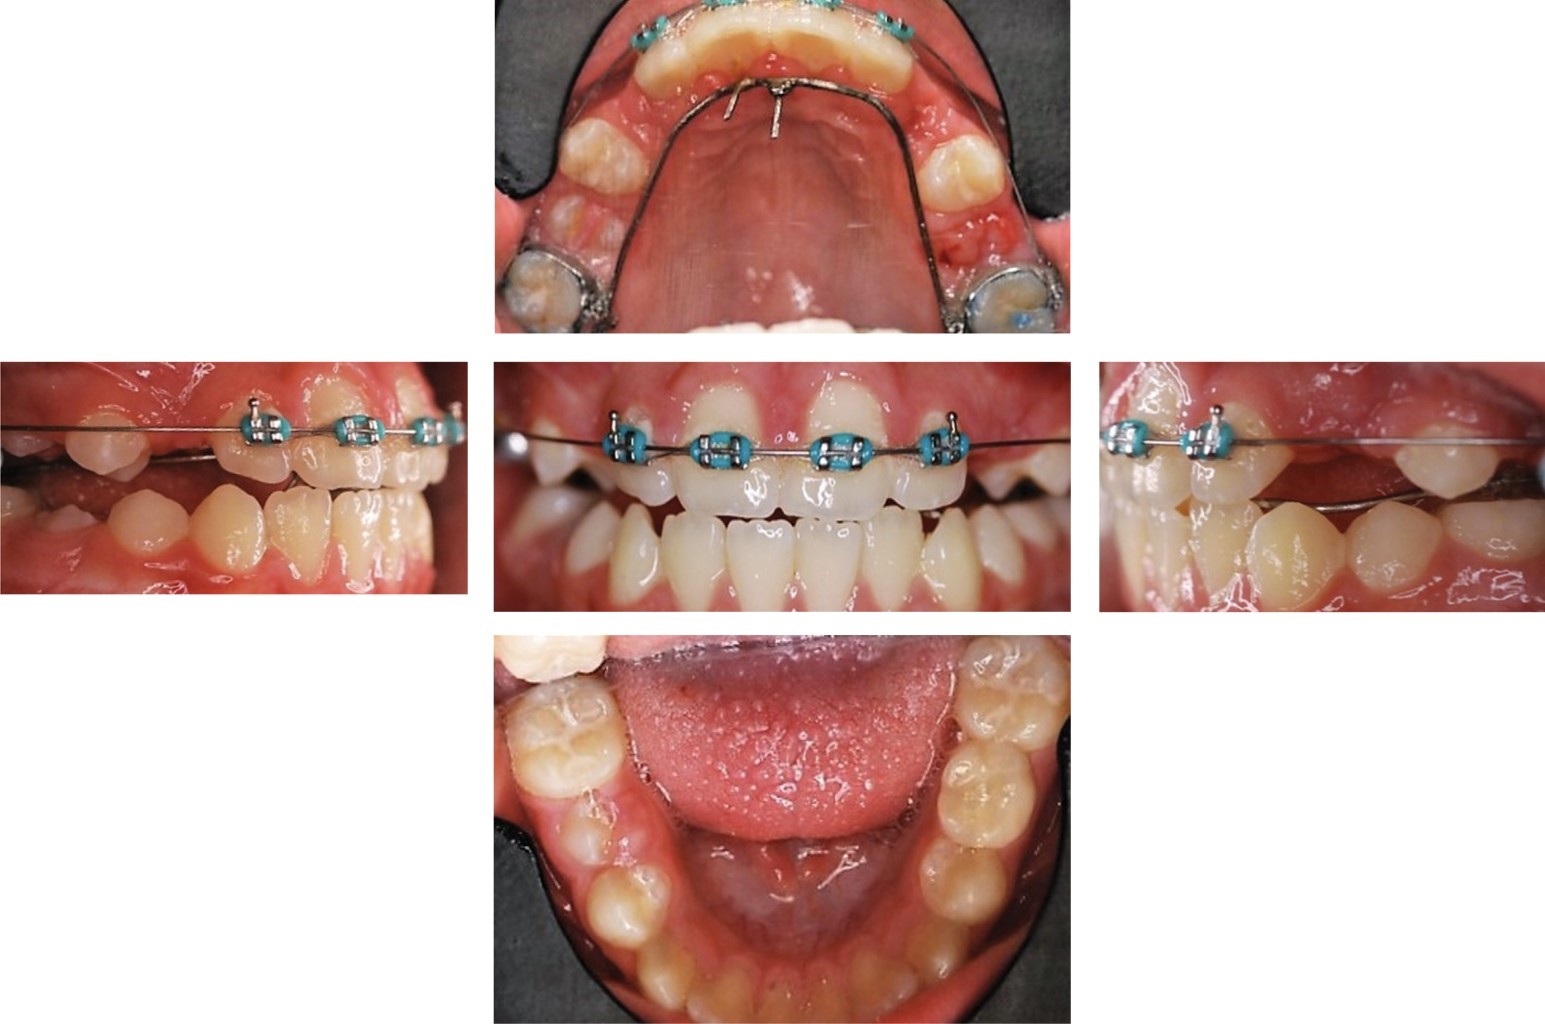

A los siete meses se realizó colocación de aparatología Alexander slot 0.018" en superior y se suspendió uso de arco lingual inferior.

Posteriormente, se cementaron brackets de los órganos dentales #14 y #15 con resorte para distalizar el órgano dental #14, se consolidó con ligadura metálica, y se cementaron brackets de #24 y #25 como se muestra en la Figura 6. A los 11 meses se logró espacio para los caninos superiores y se realizó la colocación de aparatología inferior de 6-6 con arco 0.016" NITI SE y colocación del bracket del órgano dental #23. El órgano dental #13 erupcionó sólo de la cúspide y se decide colocar un botón con hilo elástico al arco para traccionarlo junto con el uso de un elástico Delta izquierdo del órgano dental #23 a los órganos dentales #33 y #34 de de 3.5 oz. Cuando se logró la alineación y nivelación a los 32 meses se colocaron arcos 0.016" × 0.022" SS y del elástico en caja anterior ¼ de 6 oz.

Al término de 34 meses se dio por finalizada la etapa de detallado y asentamiento y se prosiguió al retiro de aparatología superior e inferior, colocación de retenedor fijo inferior de 3-3, circunferencial superior y toma de fotografías y radiografías finales.

Figura 6